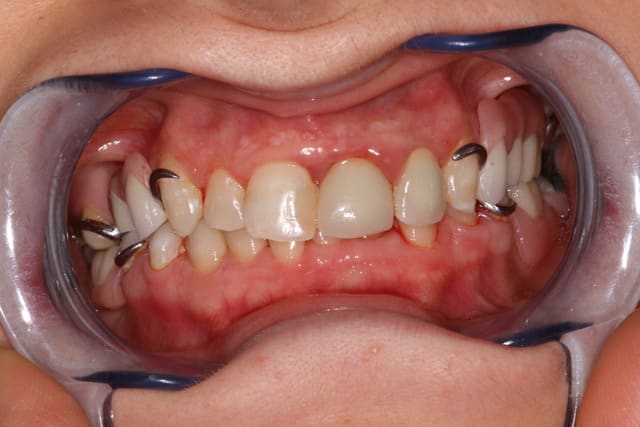

Finalement patiente revenue 8 ans plus tard et finalisée par endos, paro stellites...

Désolé je n'ai pas de belles photos de greffes osseuses comme D57 ou mes collègues implanto...

(la 22 est quasi cicatrisée pour les observateurs)